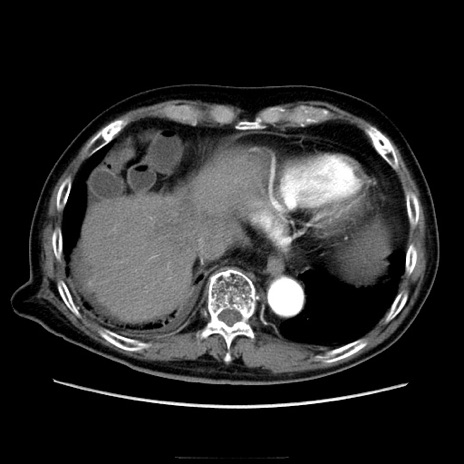

症例21(横断像)

【症例】70歳代男性

【主訴】腹痛

【現病歴】肝硬変・肝細胞癌にてかかりつけの方。約9時間前に食後より腹痛出現。症状が徐々に増悪し、嘔吐出現したため来院。

【既往歴】肝硬変、肝細胞癌(RFA、TACE後)

【身体所見】意識清明、表情苦悶様、BT 36℃、BP 129/78mmHg、P 88bpm、SpO2 97%(RA)、右上腹部から心窩部にかけて圧痛あり、反跳痛なし、筋性防御あり。

【データ】WBC 5800、CRP 0.16